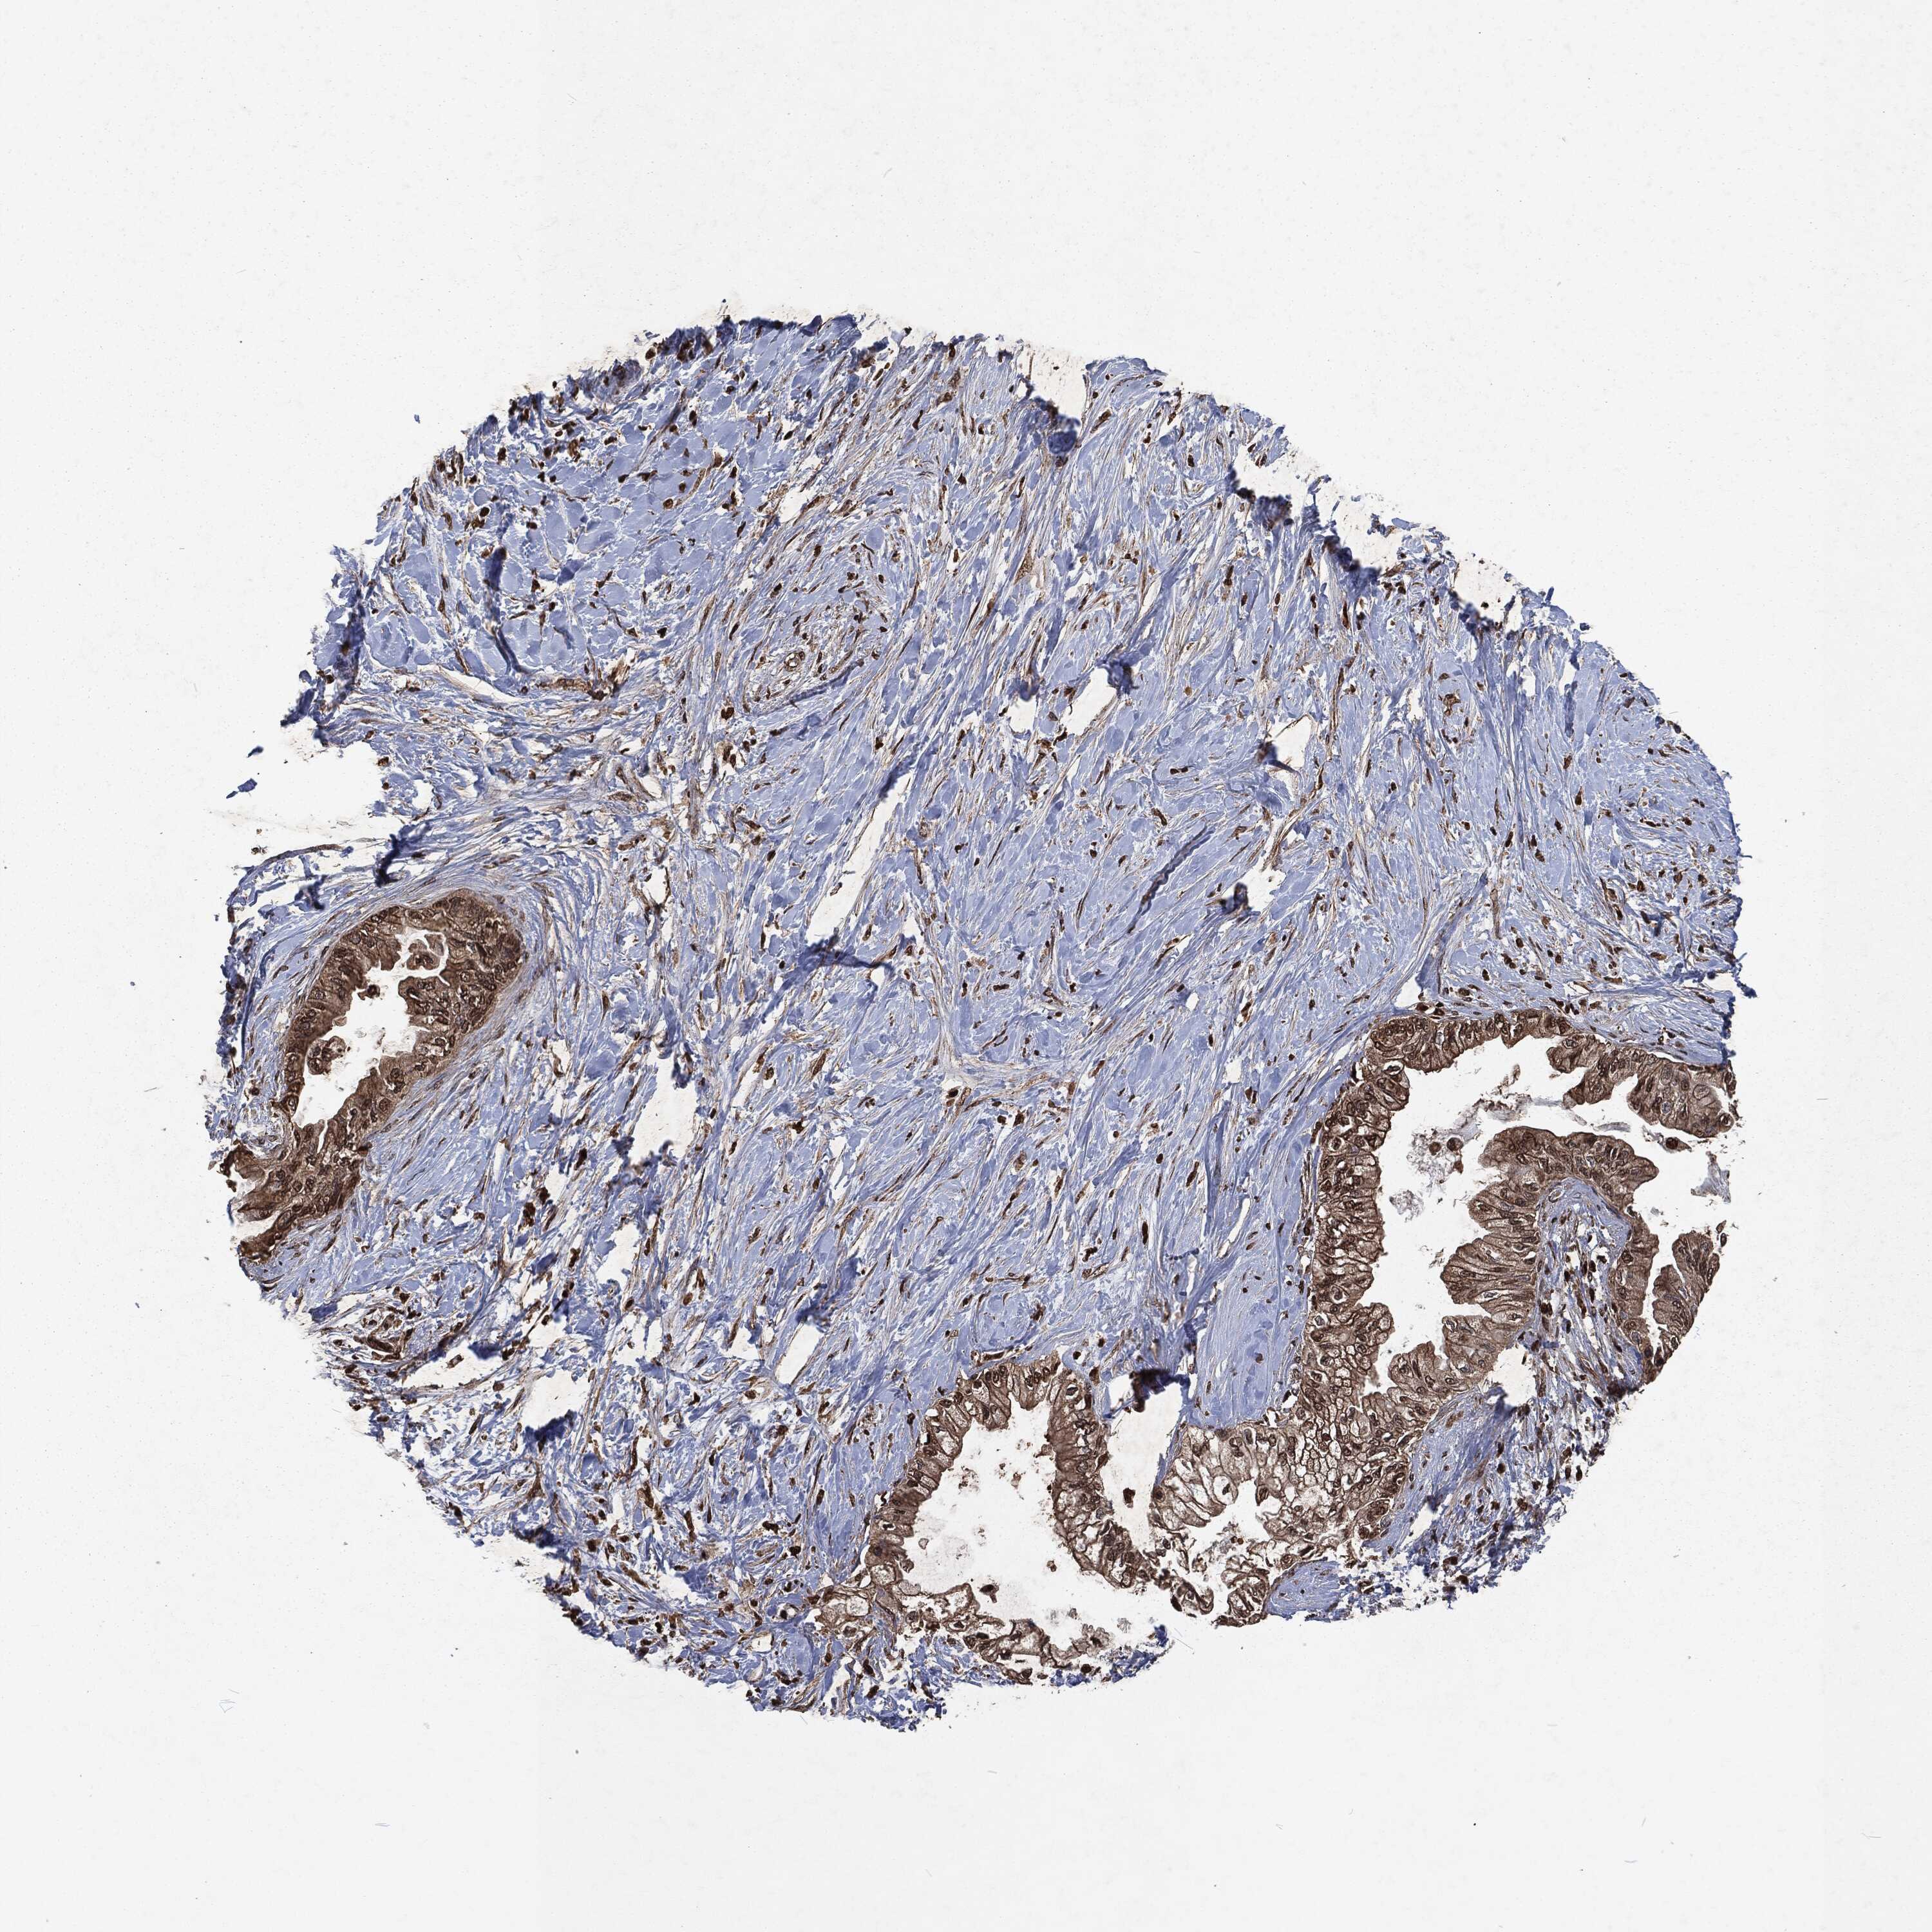

PANCREATIC CANCER - Protein expressioni

A mouse-over function shows sample information and annotation data. Click on an image to view it in a full screen mode. Samples can be filtered based on level of antibody staining by selecting one or several of the following categories: high, medium, low and not detected. The assay and annotation is described here.

Note that samples used for immunohistochemistry by the Human Protein Atlas do not correspond to samples in the TCGA dataset.

Antibody stainingi

Antibody staining in the annotated cell types in the current human tissue is reported as not detected, low, medium, or high, based on conventional immunohistochemistry profiling in selected tissues. This score is based on the combination of the staining intensity and fraction of stained cells.

Each image is clickable and will lead to virtual microscopy that enables deeper exploration of all samples and also displays staining intensity scores, fraction scores and subcellular localization as well as patient and tissue information for each sample.

Antibody HPA069985

Antibody CAB005883

Antibody CAB078687

Antibody CAB080398

Staining

High

Medium

Low

Not detected

Intensity

Strong

Moderate

Weak

Negative

Quantity

>75%

75%-25%

<25%

None

Location

Nuclear

Cytoplasmic/membranous

Cytoplasmic/membranous,nuclear

Adenocarcinoma, NOS

Adenocarcinoma, metastatic, NOS